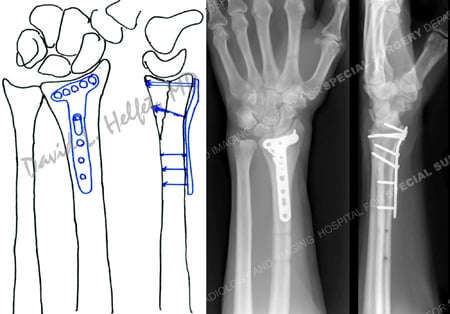

Pre-operative plan for open reduction and internal fixation with a dorsal locking plate and screws (left image) and radiographs at 6 months (right images) reveal a healed distal radius fracture.